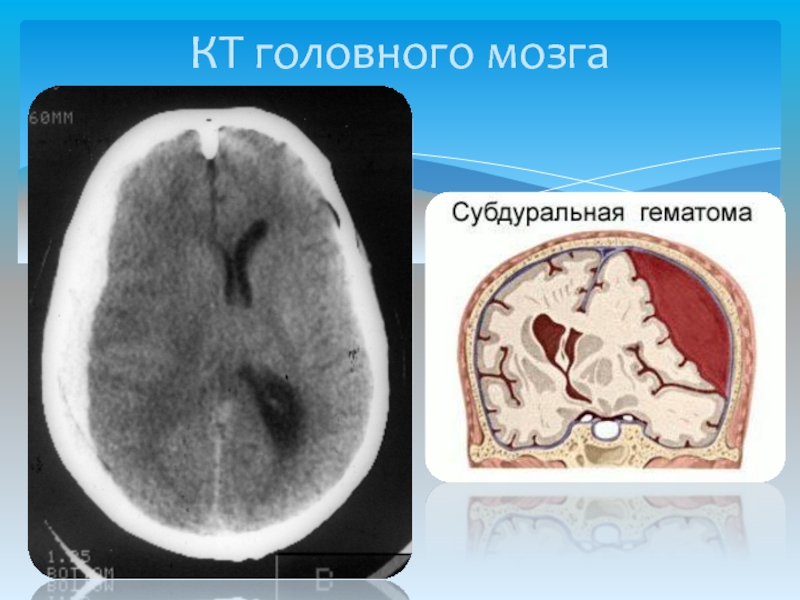

Иллюстрации и пояснения: гиподенсивный очаг на КТ головного мозга